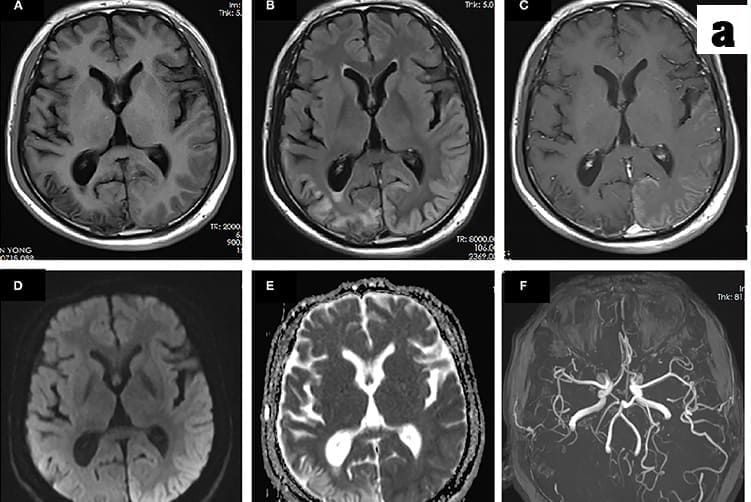

a. Migraines and TMJ disorders are diagnosed primarily through a detailed medical history and physical examination

b. For migraines, criteria from the International Classification of Headache Disorders are used, while TMJ disorders involve assessing jaw movement, tenderness and potential imaging like X-rays, MRIs or OPG to evaluate joint structure.